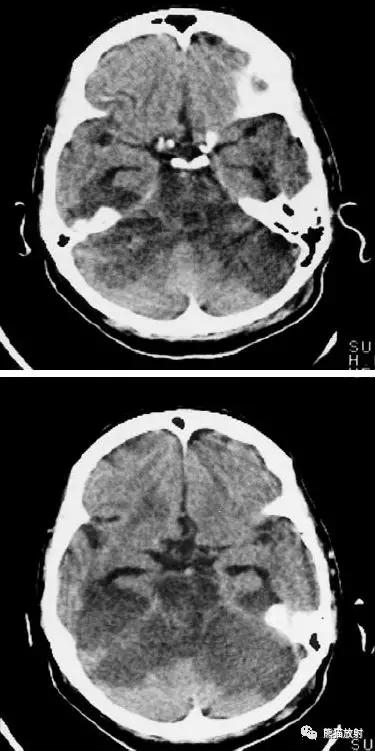

大脑中动脉区梗死:部分梗死,仅累及左侧浅表区域。

左侧大脑中动脉区完全梗死,对邻近的侧脑室产生占位效应;右侧可见其他较小的缺血性低密度区。

右侧大脑前动脉供血区部分梗死

右侧大脑后动脉供血区梗死

双侧大脑后动脉供血区梗死

右侧大脑前、中动脉供血区梗死,可见明显占位效应。